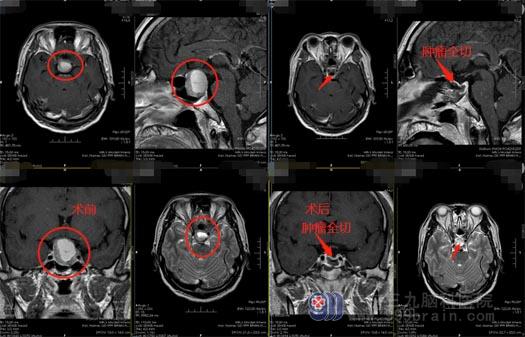

苏先生在3月前出现阵发性的头痛,休息后可以缓解,所以也就没有重视。10天前,他突然出现双眼视物模糊,当地医院头颅MR检查提示“鞍区占位,考虑垂体瘤”,需要手术治疗。

完善术前准备后,鲁明带领团队在全麻下为苏先生实施了“全麻下内镜经鼻蝶鞍区占位切除术”,手术很顺利。苏先生非常满意手术效果,不用开颅,不用剃头发,没有留下难看的疤痕,也没有手术后遗症,感觉只是睡了一觉,就把问题解决了。